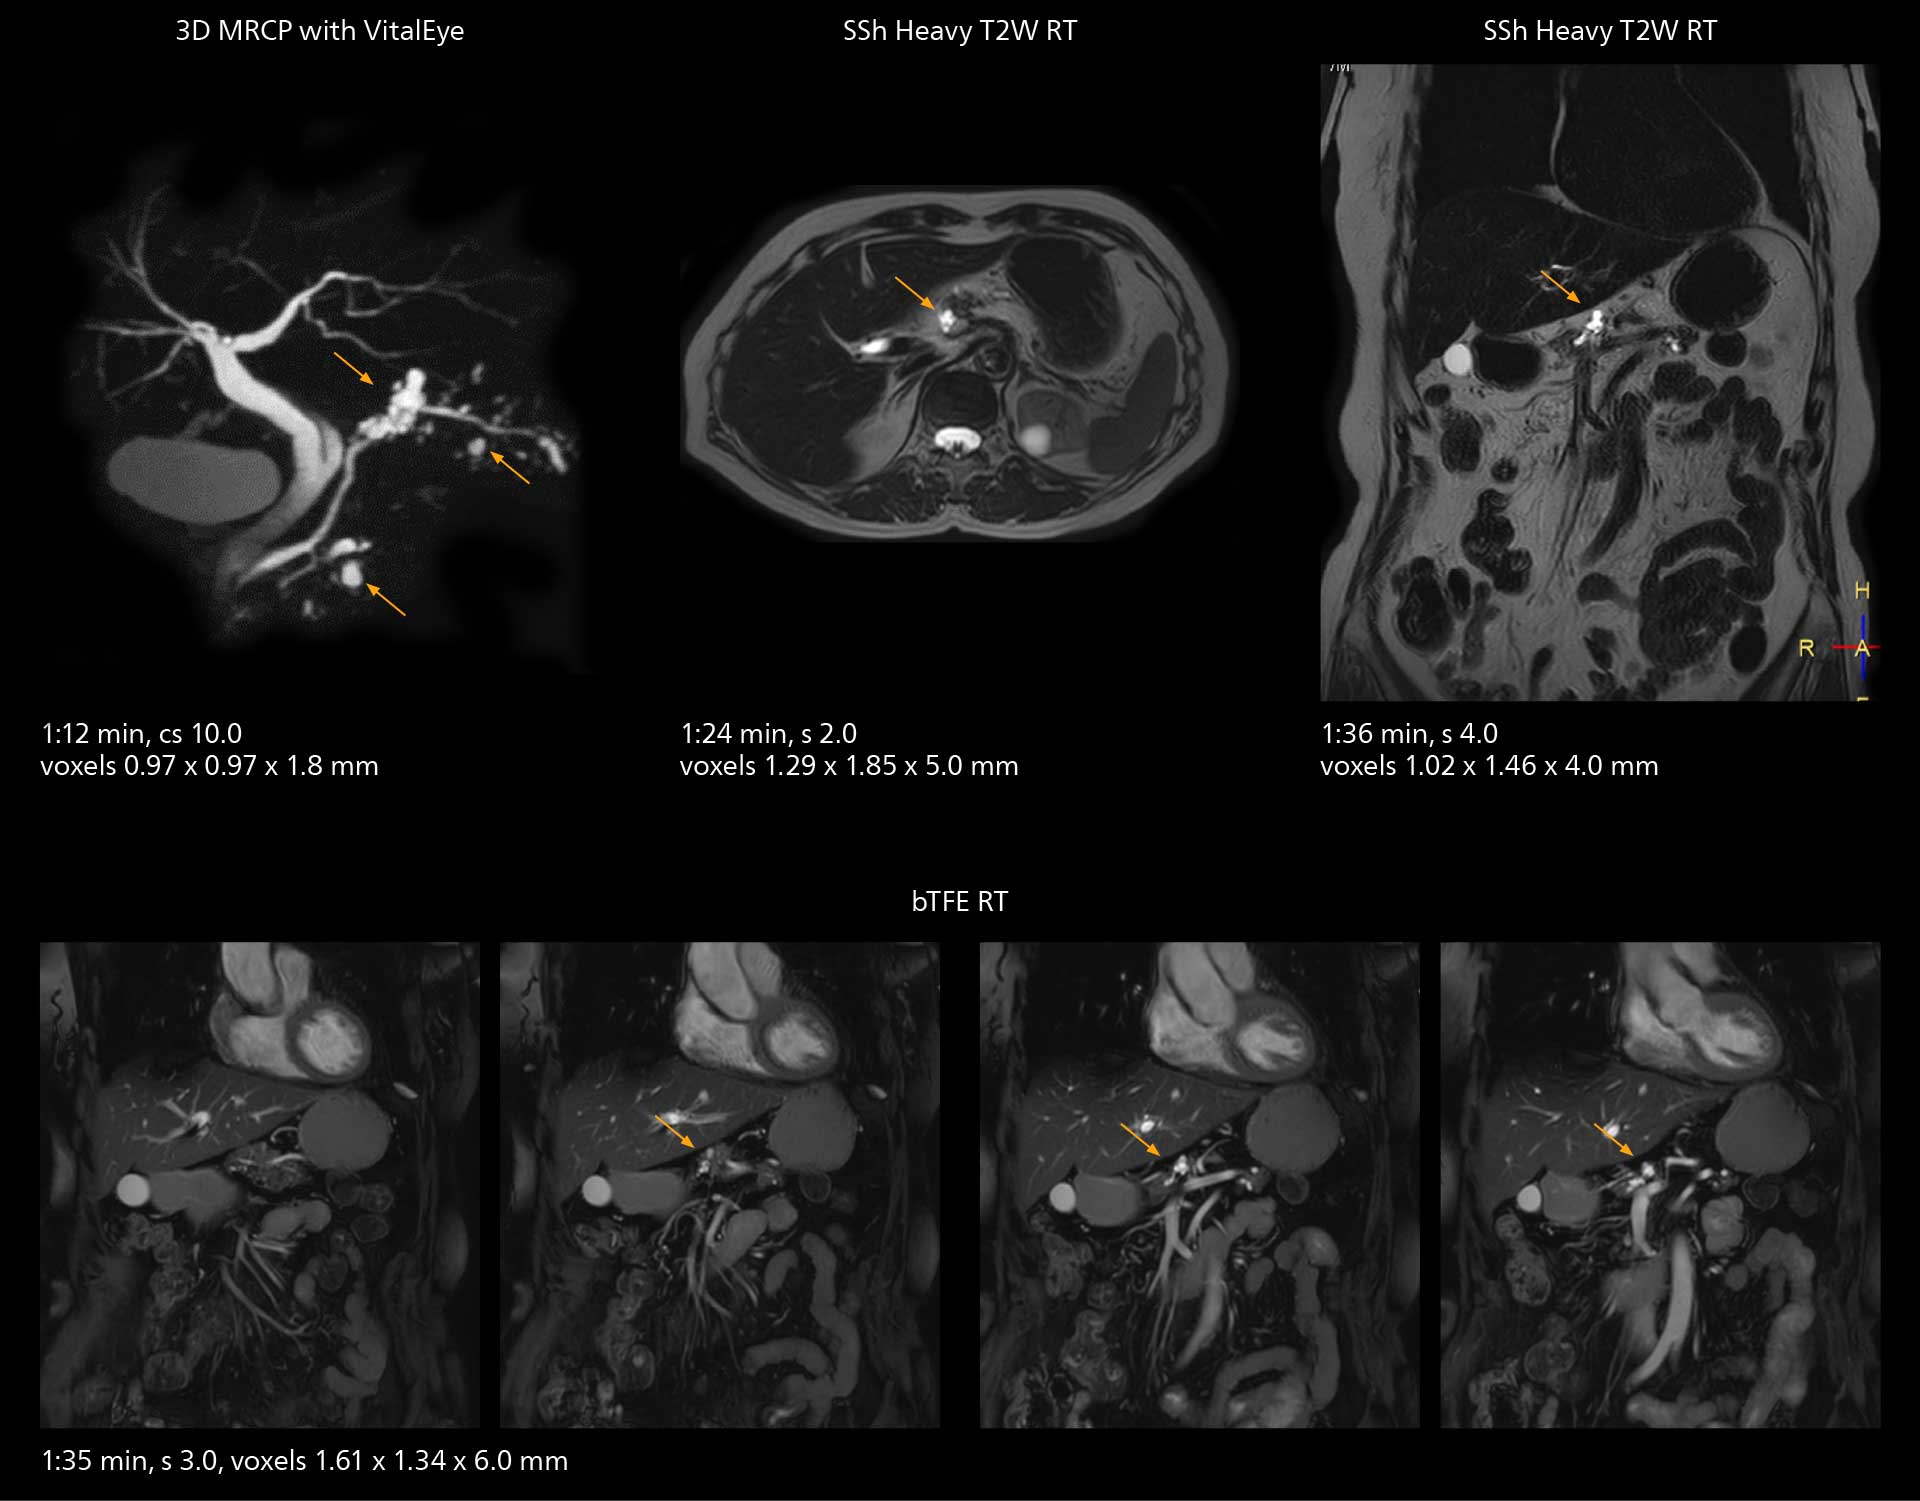

“The implementation of VitalEye respiratory synchronization has had a significant impact,” says MR technologist Yoshihiro Otsu, Chief of the Radiological Department. “It not only improves workflow, but it also has increased the quality of examinations. Particularly for the large number of MRCP examinations performed in this hospital, VitalEye has increased the possibility to obtain sharp images with less blurring. Clinicians here really appreciate this improvement in MRCP image quality.”

MRCP

With SmartPath to Elition X, the MRCP examinations at Sannodai Hospital benefit from VitalEye: respiratory synchronization is possible without respiratory belt positioning and image quality is excellent.